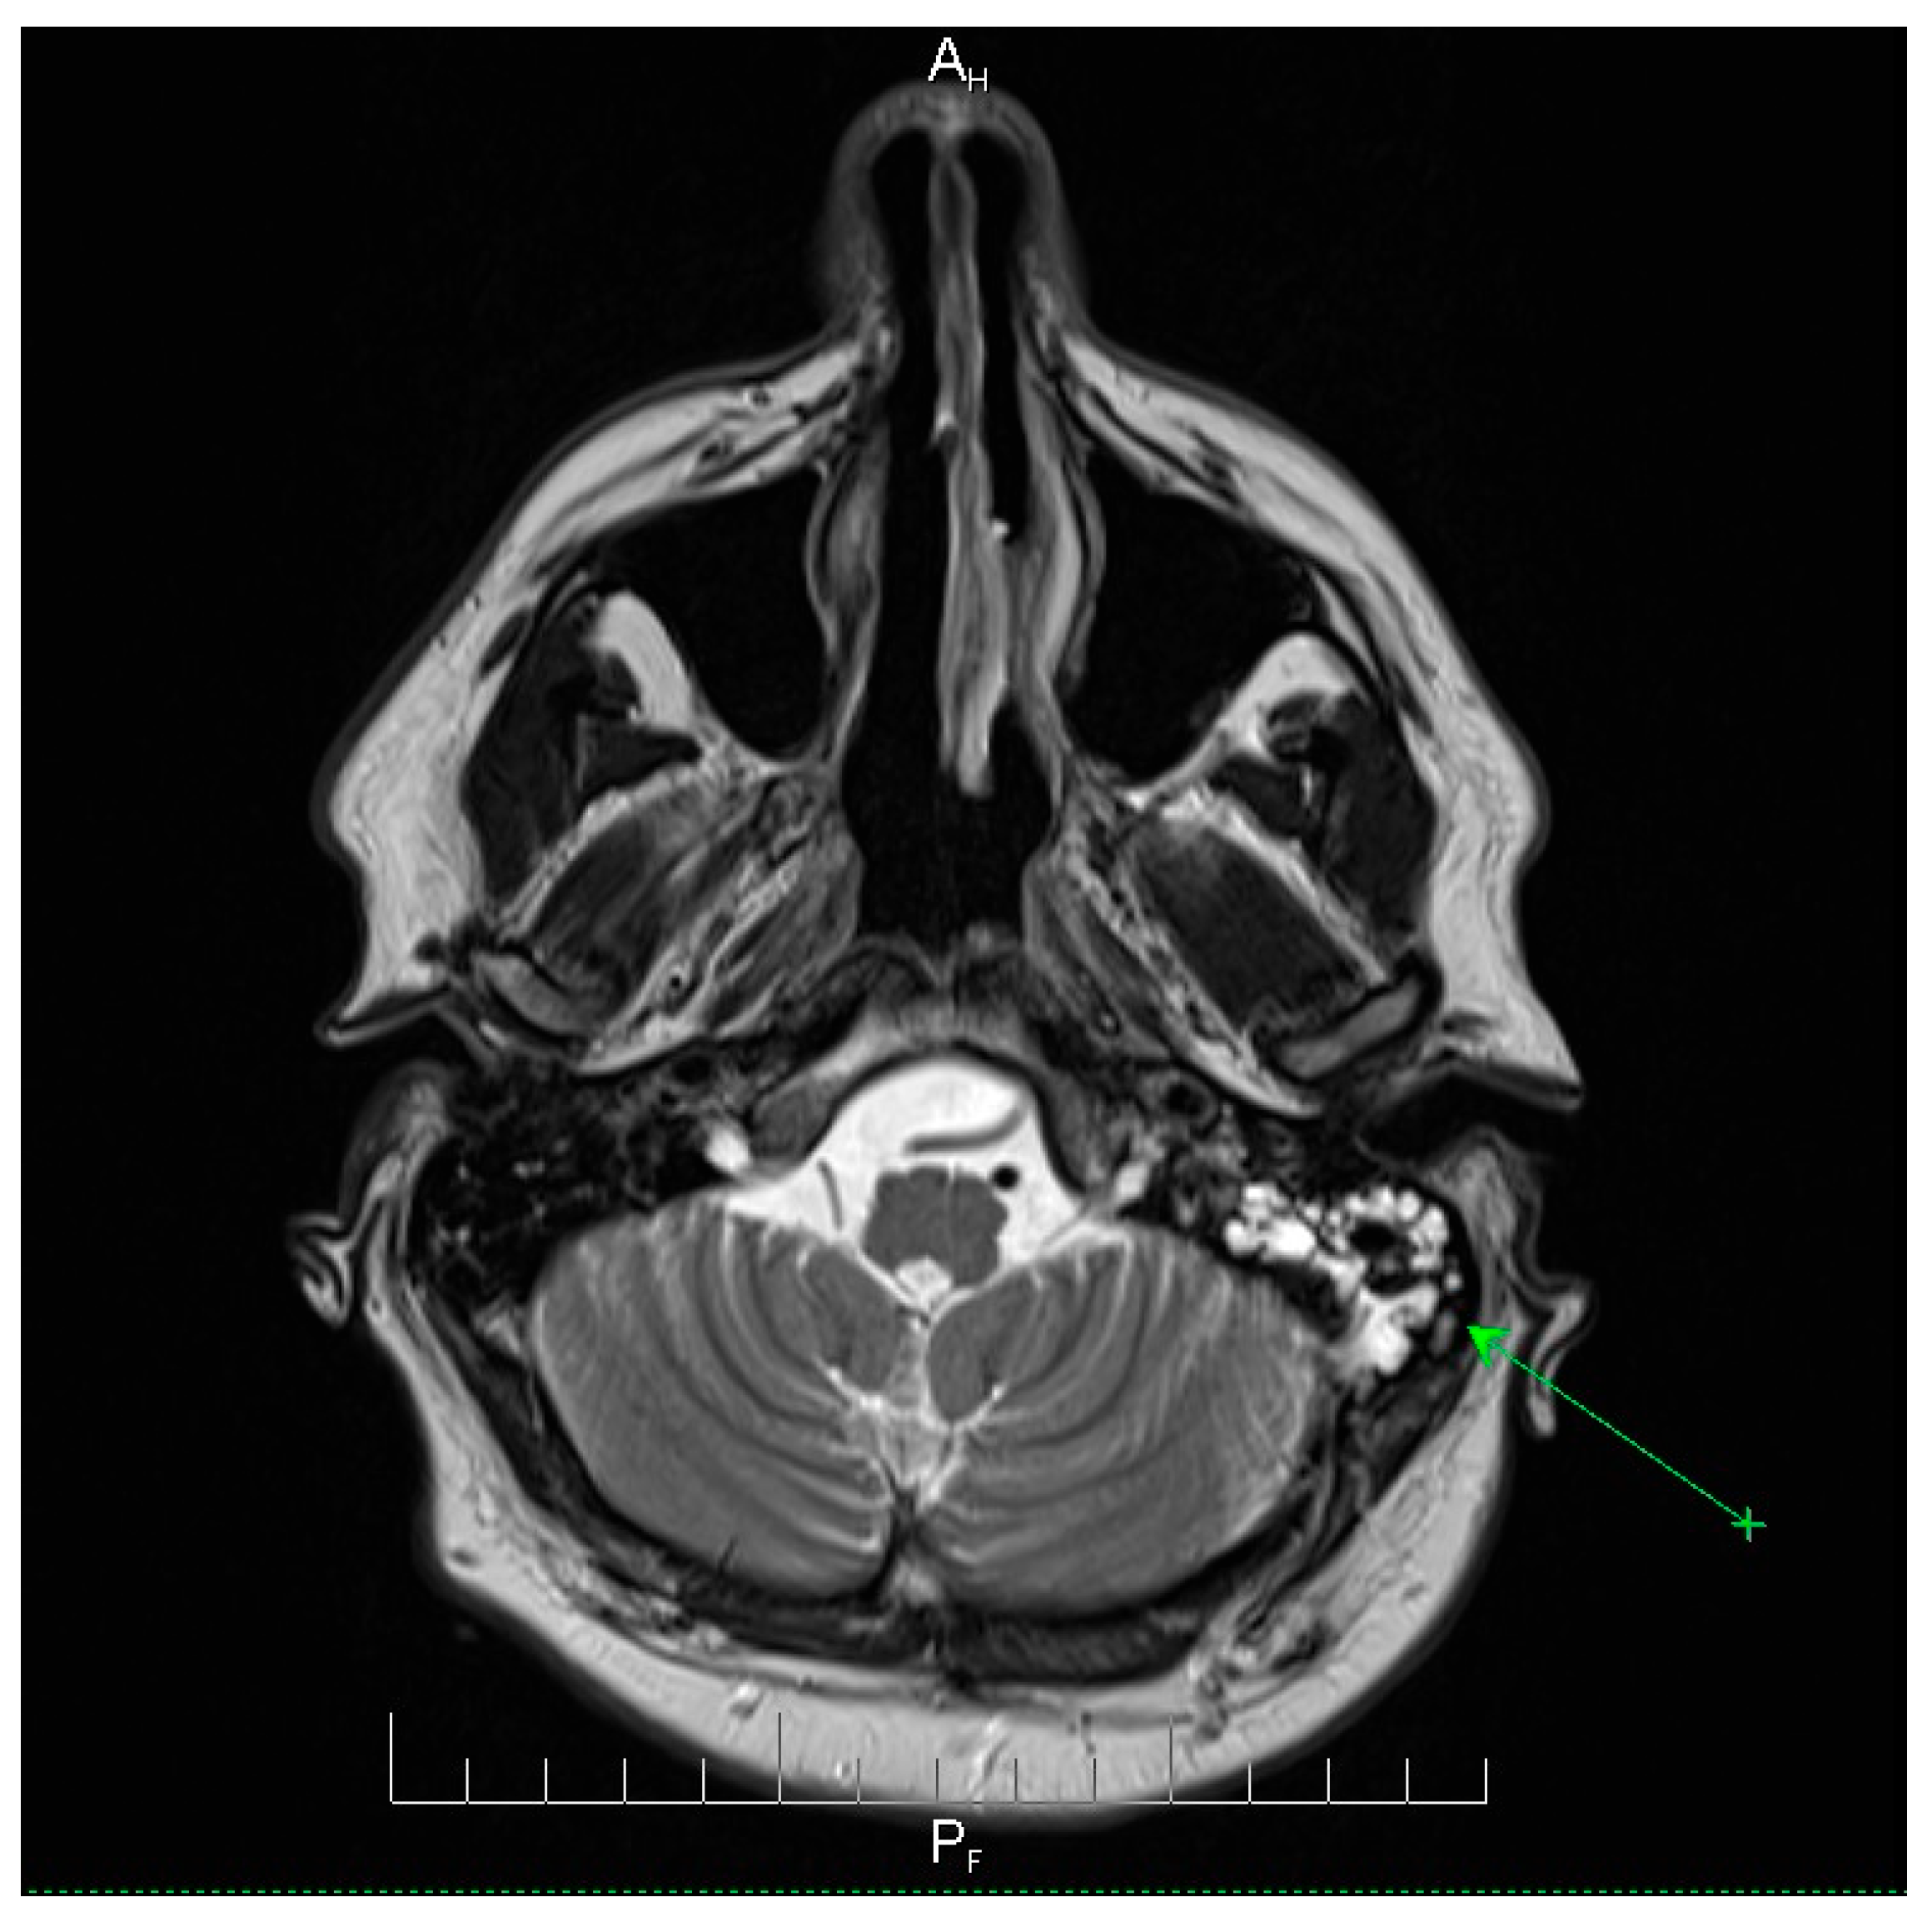

Neuroimaging revealed mild ethmoidal/sphenoidal sinus opacification and left mastoid air cell involvement without evidence of parenchymal lesions or venous sinus thrombosis (Figure 1, Figure 2 and Figure 3). Coronal and axial T2-weighted MRI sequences revealed para-fluid collections within the left mastoid air cells extending toward Citelli’s angle (Figure 1, Figure 2 and Figure 3), consistent with an otogenic focus and a possible contiguous route for intracranial spread.

Figure 2.

Axial T2-weighted MRI scan demonstrating opacification of the left mastoid air cells with a hyperintense signal (green arrow), indicative of mastoid involvement. This finding suggests a potential contiguous source of intracranial infection in this patient. No acute lesions, hemorrhage, or signal abnormalities were observed in the cerebellum or brainstem, and the surrounding brain parenchyma appeared normal. These imaging features support localized mastoid pathology without evidence of intracranial extension, providing important radiological context for the patient’s clinical presentation and aiding in the assessment of the infection risk. AH = anterior-head. PF = posterior- foot.